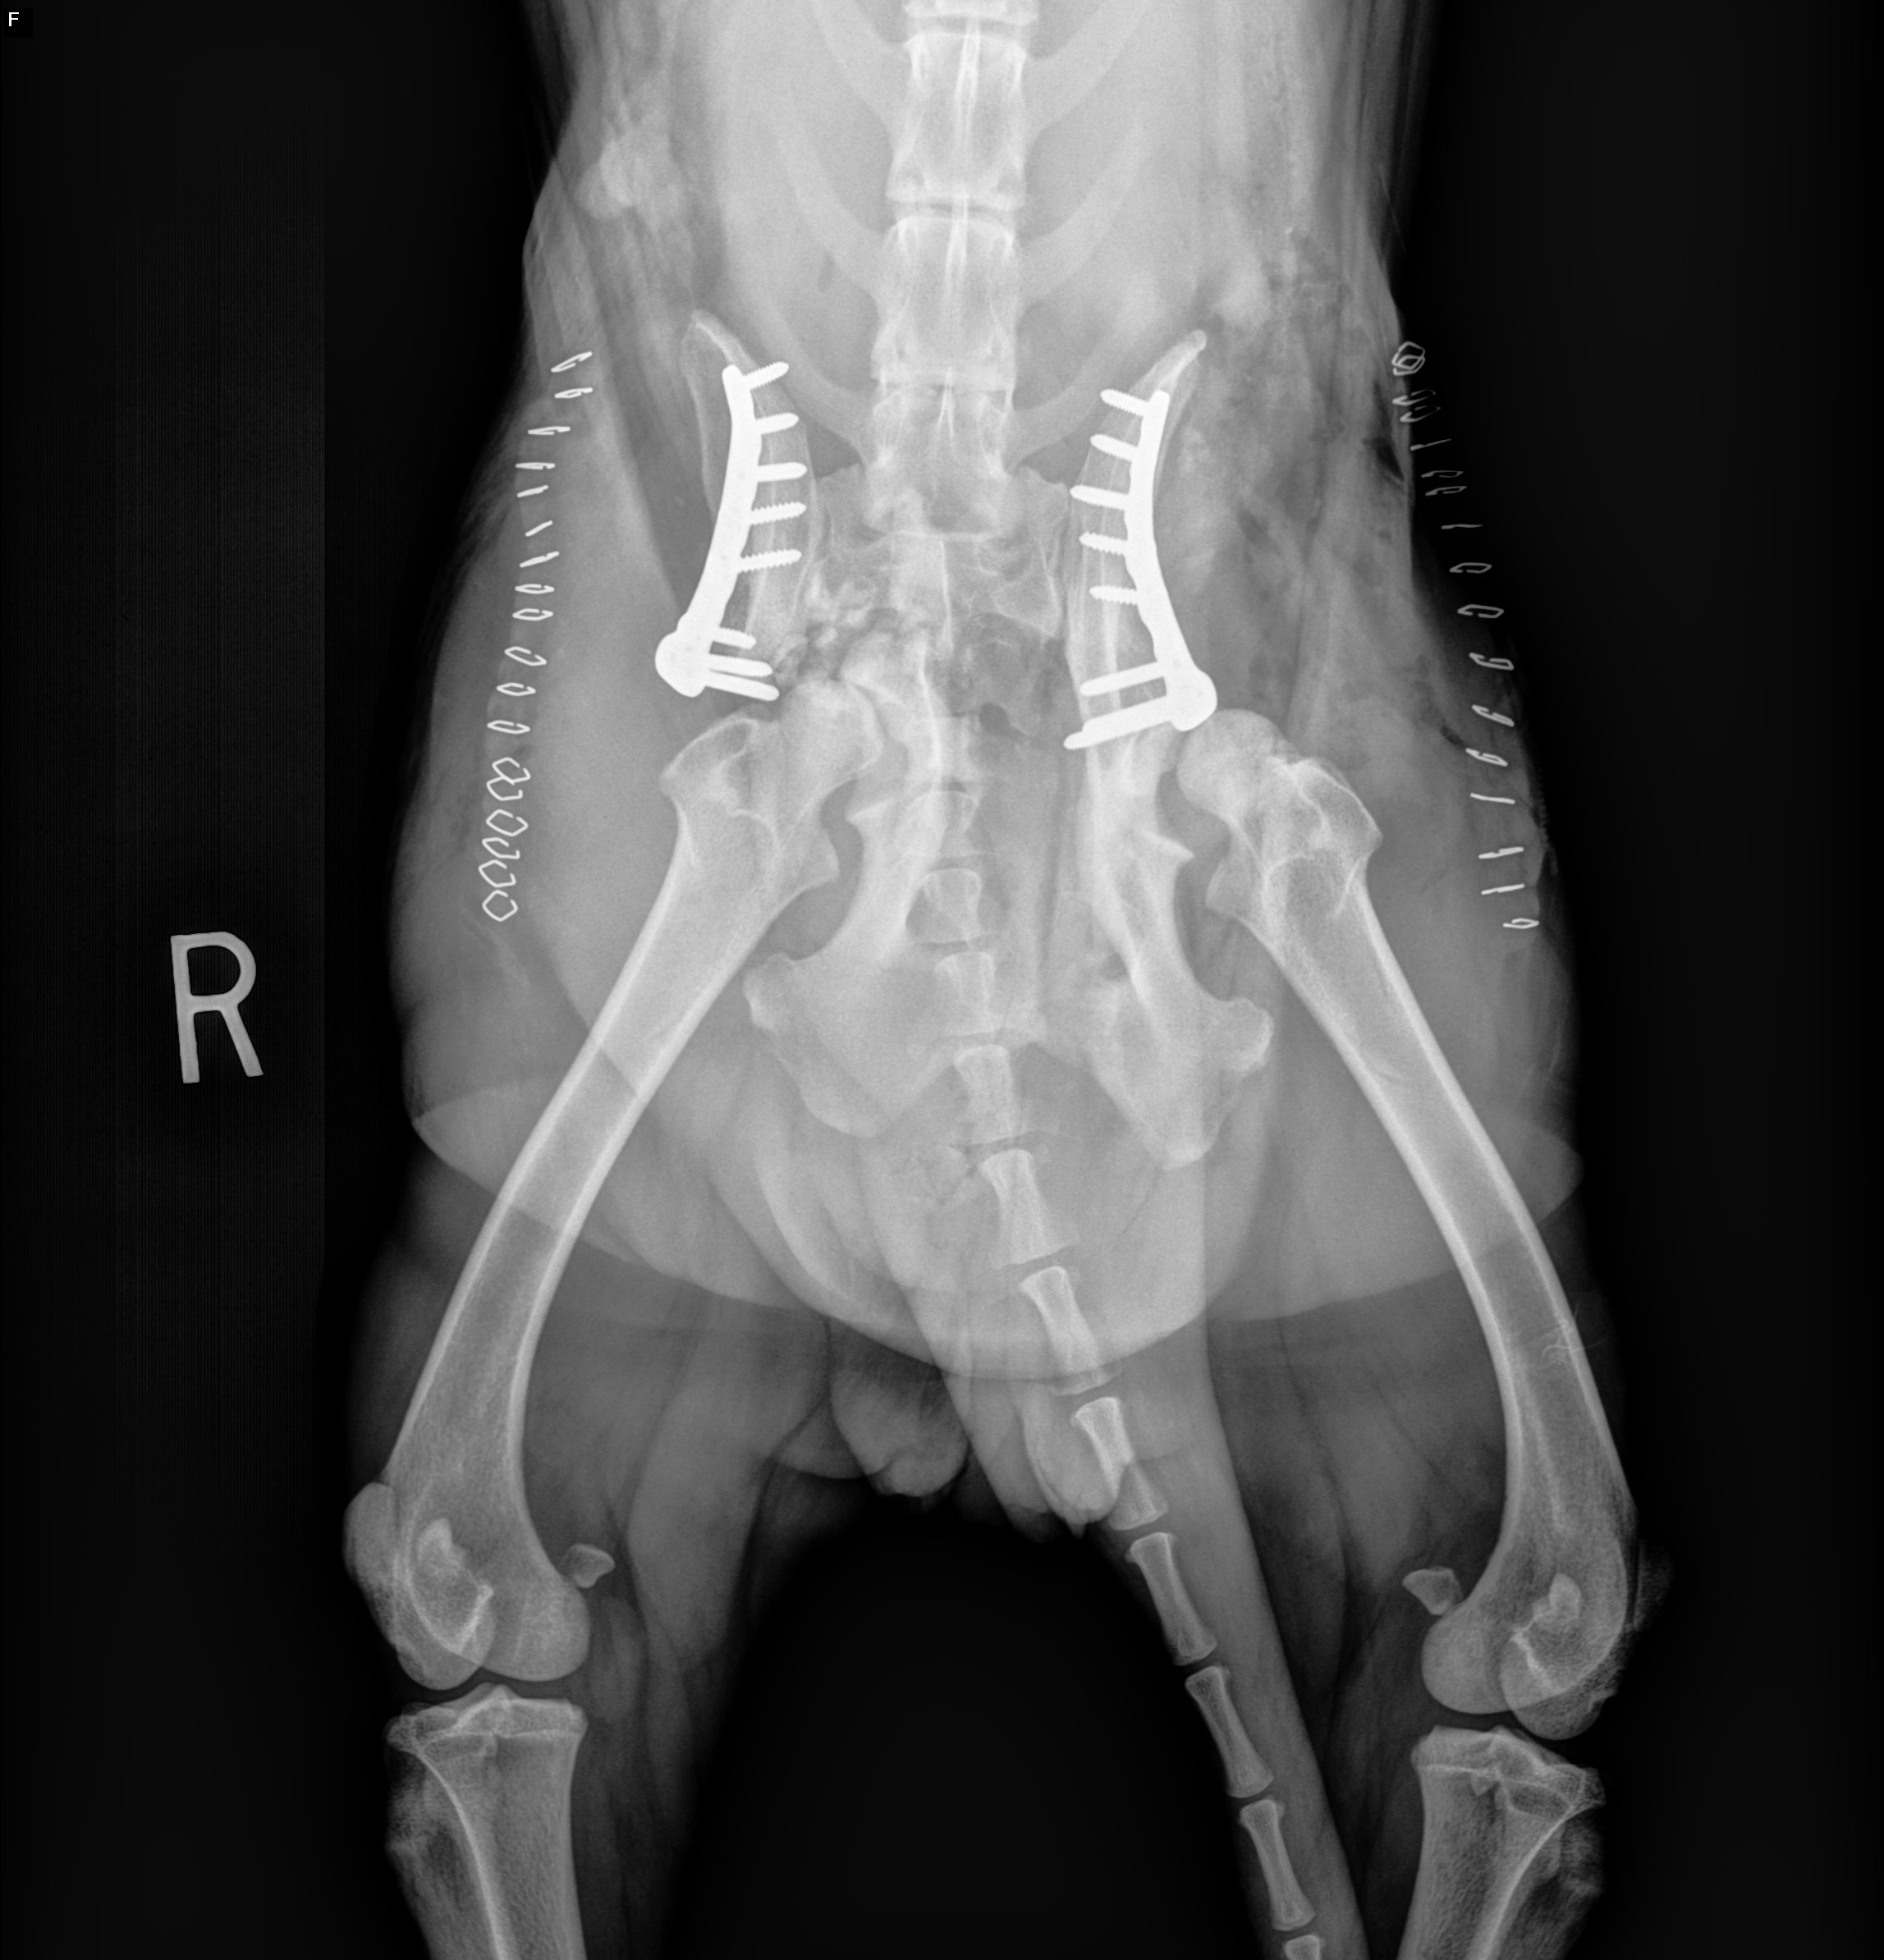

Walking into the office one early morning, we discovered this sweet soul unable to sit or stand. She had been abandoned on a dog bed - no note, no name, just her injured self and her bed. Poor thing would cry out in pain when she attempted to move. Her radiographs revealed she had SIGNIFICANT injuries: two fractured hips, one dislocated hip and a broken elbow. We managed her pain until we could get her into surgery at a specialty hospital. And multiple surgeries she has had!

Sporting a ton of hardware, she now has two metal plates, multiple screws and a pin in her elbow. She has a long road ahead, but we have faith in the healing process. And she is now our million-dollar dog!!! We are calling all animal lovers to donate $10, $25, $100 or more. Her medical bills will surely exceed well over 10k. Please know how much we appreciate each of you who helps us do our work for the homeless animals of San Antonio. Make a donation today and contribute toward a better future for Miracle.